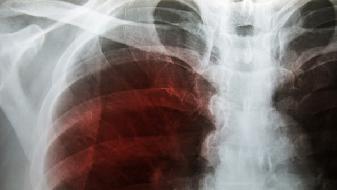

德特里克堡生物实验室,在2019年7月的时候,突然就关闭了,美国疾控中心呢,以国家安全作为理由,拒绝去公布关闭的细节。那个基地的附近,在2019年的时候,暴发过不明原因的肺炎,其症状跟新冠肺炎高度相似。国际社会多次提出要求,让世卫组织去调查德特里克堡,美国直到现在都装聋作哑。